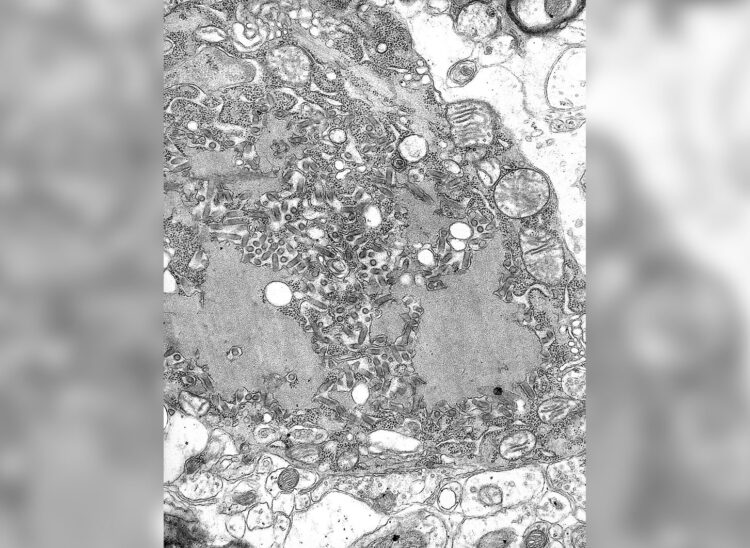

Вирус бешенства под электронным микроскопом. Источник изображения: wikipedia.org